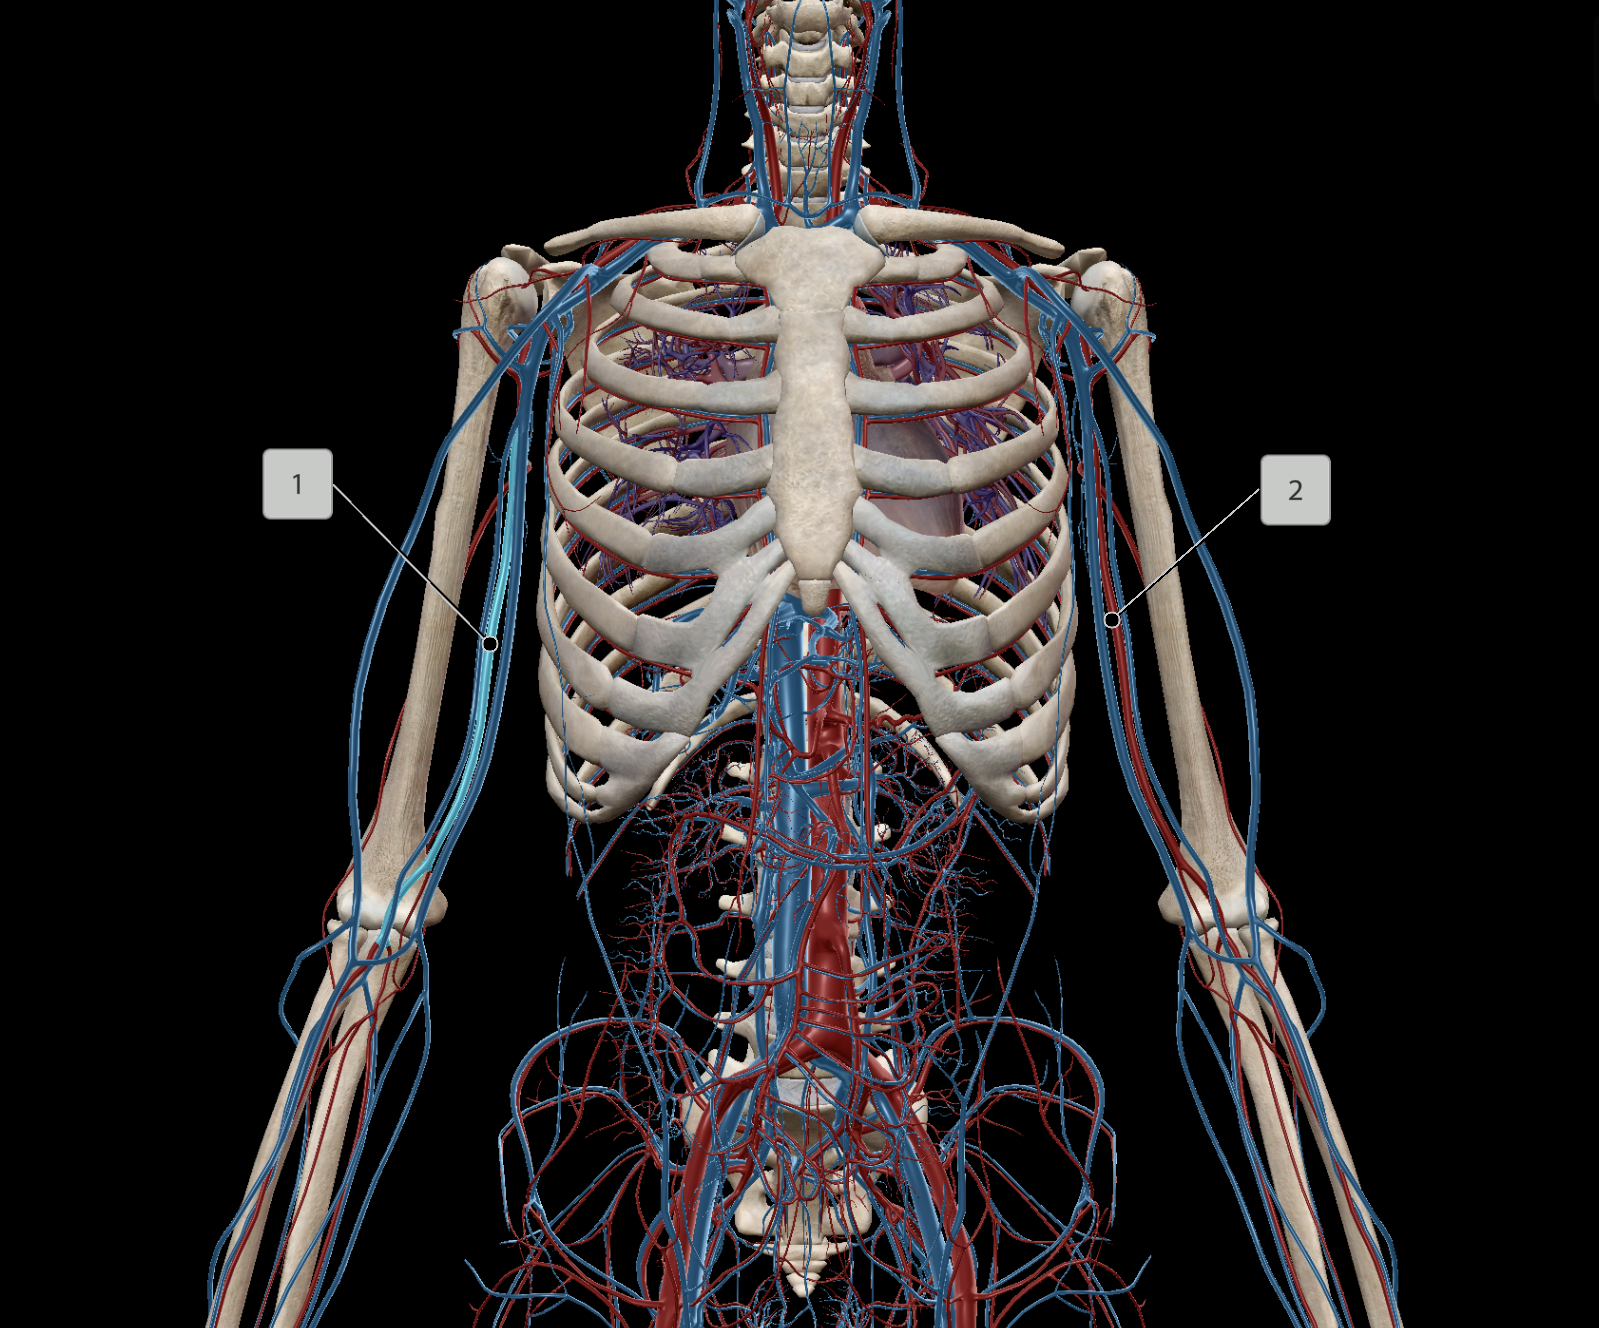

Brachial Artery

Ulnar Artery

Radial Artery

Axillary Artery

Brachial Vein

Axillary Vein

Subclavian Vein

Radial Vein

Ulnar Vein